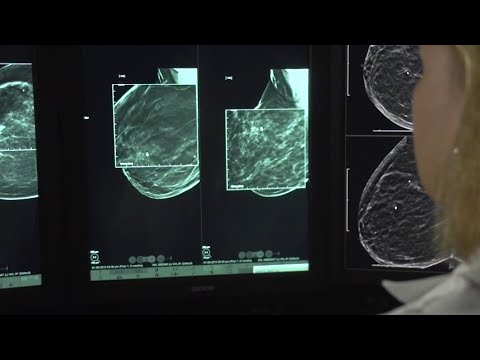

NHS Cancer Screening Programmes